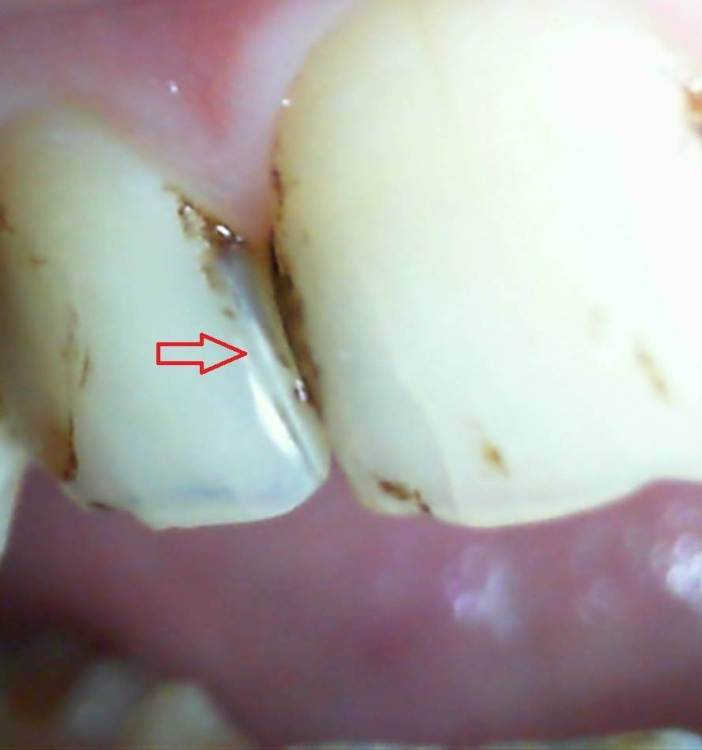

На 26-й день при умеренной жевательной нагрузке (решил покончить с зависимостью от чипсов и употребил четыре больших и одну среднюю банку Pringles - однако никакого жёсткого накусывания и никакого звука трескающегося зуба не происходило) - образовалась наклонная вертикальная трещина, заходящая на режущий край, что ощущается языком (фото 1-5). Удивительным образом, характер боли после этого практически не поменялся.

Я вспомнил, что врач после постановки пломбы с большим дёргающим усилием вытаскивал именно со стороны зуба №11 некий формирующий элемент. Скорее всего, это была не т.н. матрица, а нечто предыдущего поколения, вроде металлической пластины.

Отмечу также, что пломба имеет нависающий край, о который разволокняется зубная нить, и некий карман, куда попадают остатки пищи.  Читал, что нависающий край пломбы образуется, когда врач не использует матрицу и матрицедержатель, а использует металлическую пластину. Также сама пришеечная часть ощущается "заострённой", нежели округлой.